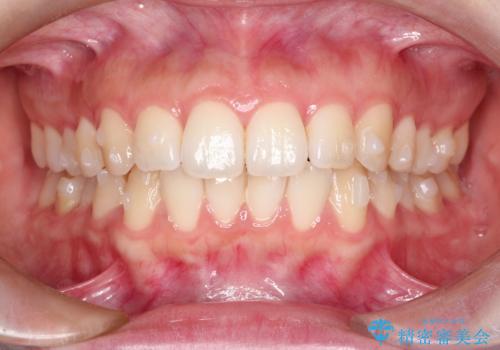

前歯のがたつきをインビザラインで目立たない矯正

- 上下の前歯のがたつきを主訴に来院されました。

マウスピースでの矯正を希望されたので、インビザラインで矯正治療を行うこととしました。

インビザラインではシュミレーションによりどのように歯が動くかを確認して矯正することができるので、患者様も安心して矯正をすることができました。